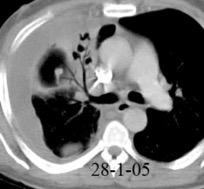

Marzo 2014: Perforación longitudinal distal secundaria a episodio de vómito (síndrome de Boerhaave). Derrame pleural izdo. que evoluciona a empiema.

Wang C-T et al. Tension hydropneumothorax in a Boerhaave syndrome patient: A case report . World J Emerg Med, 2021. Katabathina V et al. Nonvascular, nontraumatic mediastinal emergencies in adults:a comprehensive review of imaging findings. Radiographics. 2011.